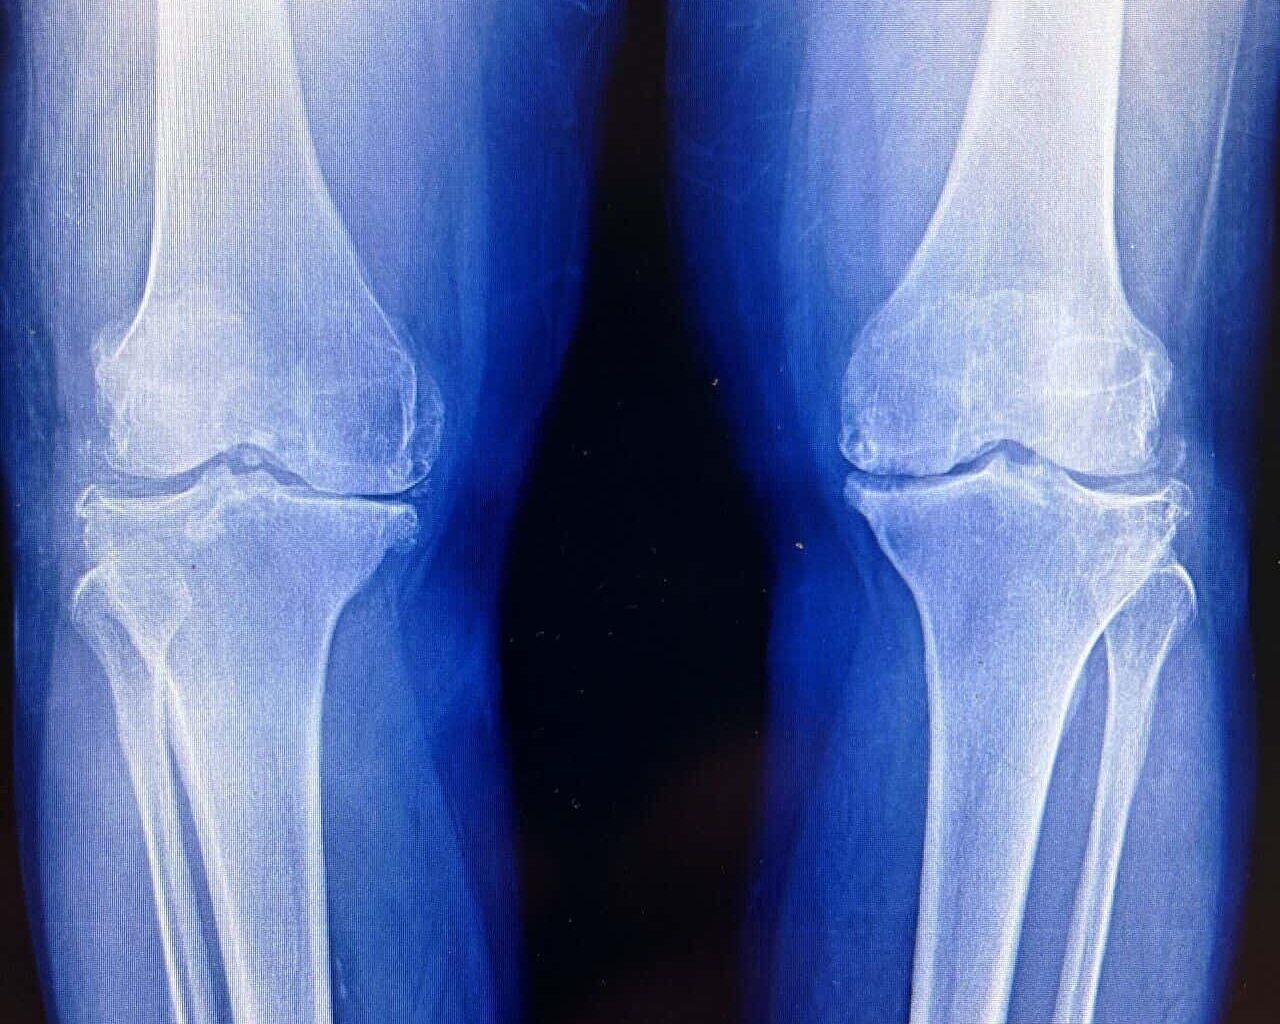

Cartilage is the body’s most stubborn tissue. Once it wears away, it’s usually gone for good. This biological dead-end is the engine behind osteoarthritis, a grueling condition that stiffens joints, fuels chronic pain, and eventually forces millions of people into the operating room for total joint replacements.

Mouse studies often raise hopes that fade once switching to people. To test whether human cartilage might respond in the same way, the researchers turned to tissue removed during knee replacement surgeries.

The findings arrive amid a broader push to develop treatments that modify osteoarthritis itself, rather than simply easing pain. About one in five adults in the United States has the disease, which estimates costs of tens of billions of dollars a year in direct health care expenses. Current drugs do little to slow cartilage loss. When joints fail, surgery is often the only option.